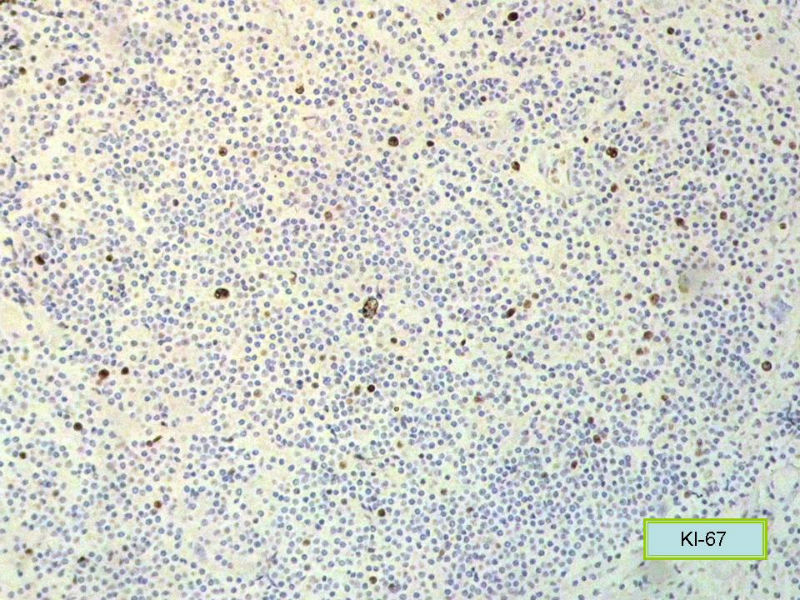

请再标记CD20和CD79a!图片中阳性不明确,根据T细胞标记看,应该是B细胞结节。Ki67散而少,不支持低级别滤泡性淋巴瘤,若B细胞弥漫阳性,则是惰性B细胞非霍奇金淋巴瘤,首先考虑套细胞,然后是边缘区淋巴瘤。不做生发中心标记,Bcl-2在小B细胞淋巴瘤分类中无意义。

CD20(+),Kappa(+),ki-67(+)>2%,Lambda(+),Pax-5(+),符合粘膜相关淋巴瘤。